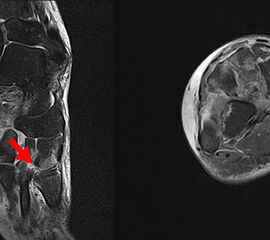

Das Lisfranc-Ligament selbst lässt sich am Besten im MRT beurteilen. Gelegentlich lässt sich im MRT ein Knochenmarksödem als einziges Zeichen einer nicht dislozierten Fraktur finden. Die MRT-Diagnostik ist allerdings eher unklaren interossären Erweiterungen bei persistierenden Schmerzen zur Suche nach isolierten Bandverletzungen vorbehalten 7511.

Zum Lesen der Bildbeschreibung und zur Vollansicht bitte das Bild anklicken.